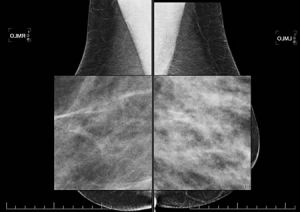

L’examen comporte 2 ou 3 clichés sur chaque sein. La compression du sein est nécessaire pour améliorer la qualité des clichés, donc l'efficacité du diagnostic radiologique. La compression est un peu désagréable. Elle est très rarement douloureuse. Si c'est le cas, la manipulatrice cessera immédiatement la compression.

Plusieurs clichés pourront être réalisés sur chaque seins.